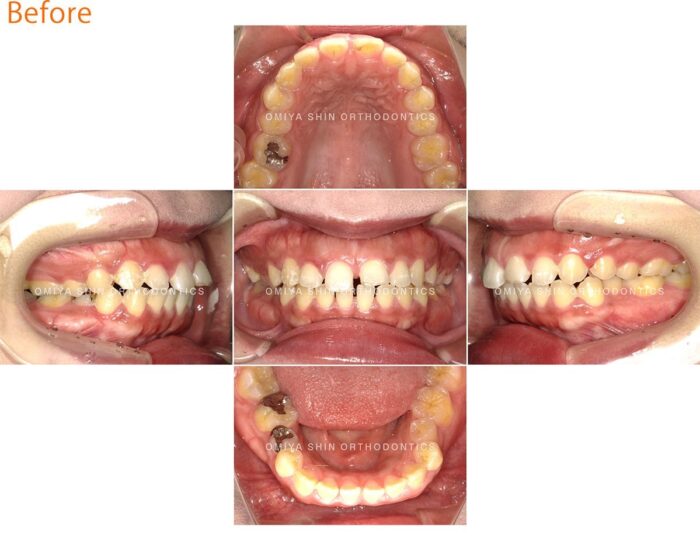

マウスピースで正中離開を矯正治療した症例

「前歯のすき間が気になる」と来院された30代の女性。見た目のコンプレックスが主な理由でしたが、歯の隙間から空気が漏れて発音が不明瞭になる、といった機能的な面での悩みもありました。

目立たない矯正装置を希望されたのでマウスピース矯正装置(インビザライン)を選択しました。

歯を内側に寄せるスペースを確保しながら、前歯を少しずつ動かす計画を立てました。

症例まとめ

- 主訴:前歯の隙間が気になる

- 診断名:空隙歯列

- 初診時年齢:32歳

- 使用装置:マウスピース矯正装置(インビザライン)

- 抜歯部位:なし

- 費用:¥850,000(税込¥935,000)

- リスク・副作用:痛み、歯根吸収、歯肉退縮、虫歯、後戻り